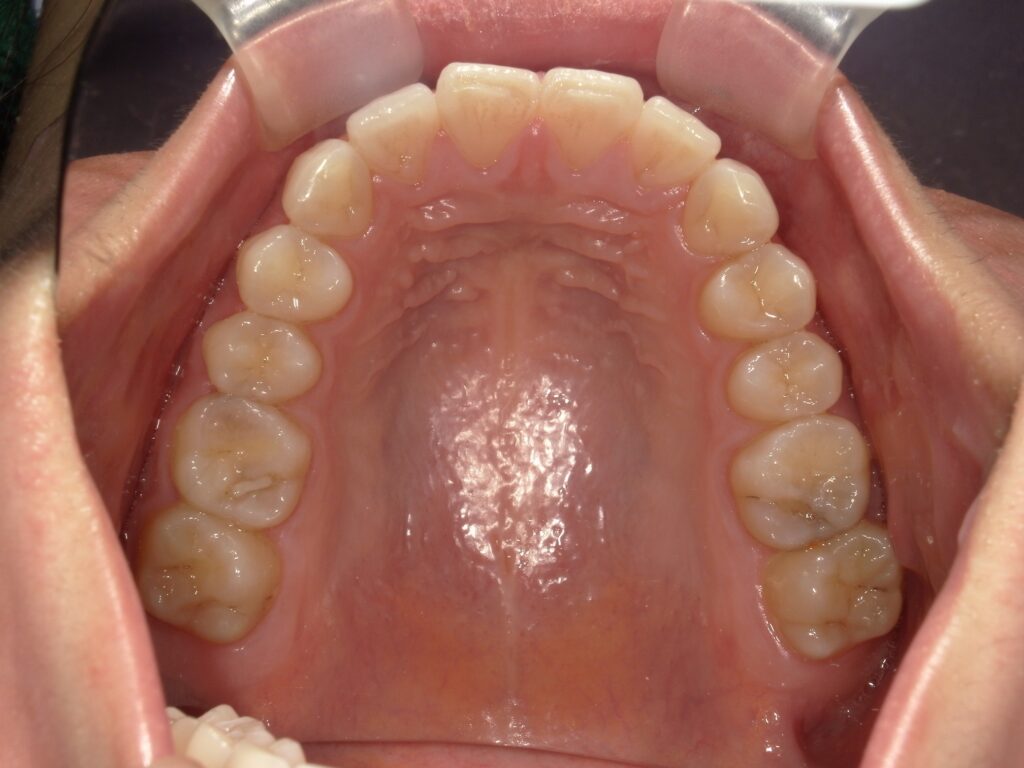

【治療前】

前歯のがたつき

この写真のように前歯のみの軽度ながたつきであれば3〜6ヶ月の治療期間で終えることが可能です!